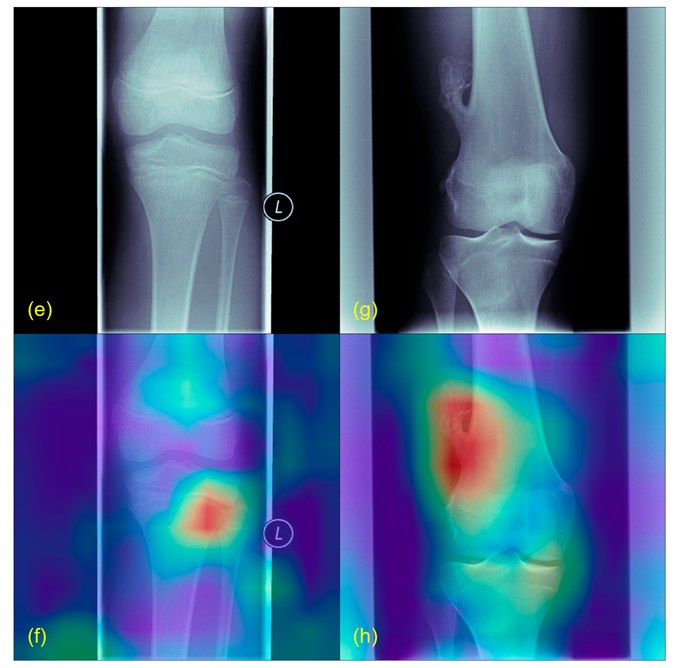

2.5. Plausibility